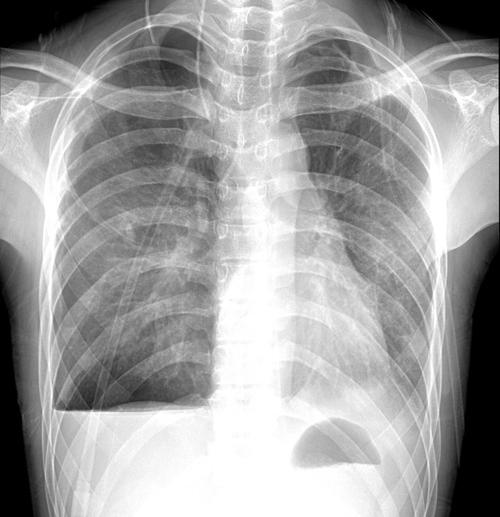

做了胸片多久可以备孕

定期的接受一系列比较全面的身体检查是对自身身体健康的一大保障,也是非常必要的教育,为了避免因为没有注意好的身体而影响到备孕的过程。那么对于怀孕的整个过程中也需要进行一定的身体检查,那么在做了胸片多久可以备孕?

做了胸片后发现怀孕了有影响吗

做了胸片后发现怀孕了有影响吗?说做了胸片后发现怀孕后,担心会影响到胎儿发育,但是又不知道能不能保留孩子?

做了胸片后,胎儿发育就已经完全了,如果做了X射线或放射性检查,则会造成胎儿畸形,因此孕妈如果接受X射线检查,最好避开怀孕的6个月后,等胎儿的发育完全后再进行备孕。